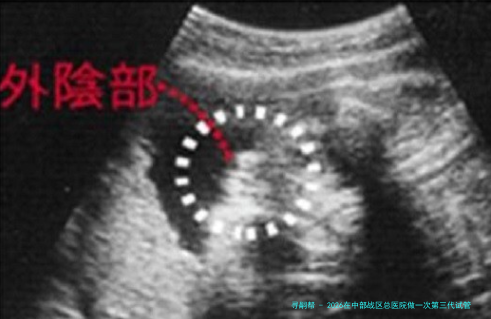

胚胎活检与筛查:对发育至囊胚期的胚胎进行活检,样品送检验进行遗传课程分数析。